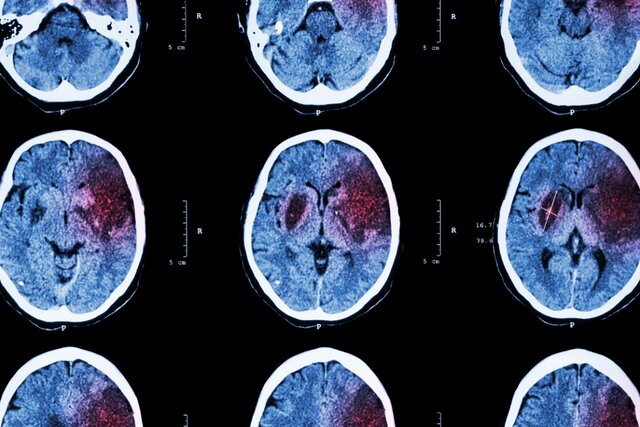

سن سکته مغزی در ایران ۱۰ سال کمتر از دنیا / سکته مغزی، دومین علت مرگ در ایرانی‌ها

سکته مغزی یکی از علل اصلی مرگ و میر در جهان محسوب می‌شود و نه تنها برخی از مبتلایانش را به کام مرگ می‌کشاند، بلکه افراد بسیاری هم در اثر این عارضه دچار ناتوانی‌هایی می‌شوند که تا پایان عمر همراه همیشگی آنها است.